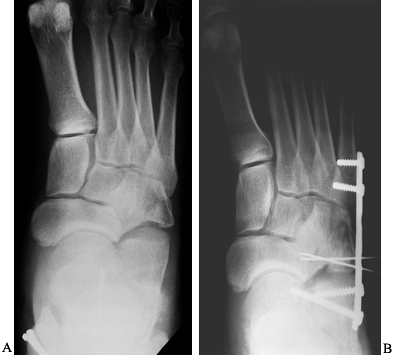

Figure 111.5. A: Cuboid fracture with impaction of the proximal articular surface. B: Operative radiograph showing the use of a bridging plate, threaded K-wire, and bone graft. -